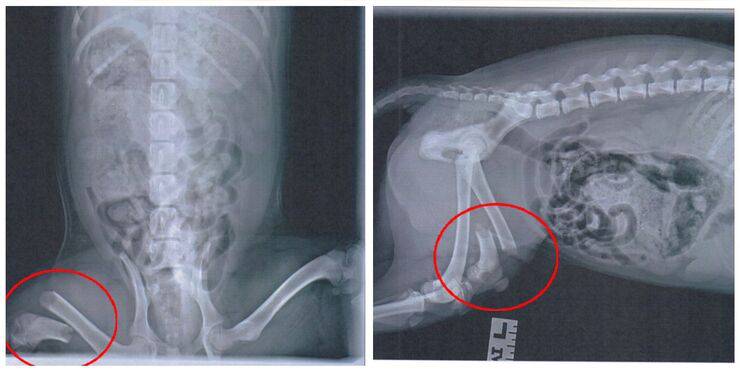

Il cucciolo è stato immediatamente portato presso campus della South Mountain dell’Arizona Humane Society dove i veterinari stanno procedendo con le migliori cure per il piccolo , sfortunatamente dai raggi x si è potuta riscontrare l’entità del danno subito dal cucciolo infatti la zampa posteriore del cucciolo era rotta.

Su un post facebook pubblicato dalla Arizona Humane Society si legge infatti che sfortunatamente la zampa del piccolo Golden retriever di soli 3 mesi non poteva essere sistemata mediante un intervento chirurgico, e che a causa delle ferite riportate l’unica soluzione era quella di amputare la zampetta.

“I nostri veterinari dell’ospedale traumatologico hanno stabilito che l’amputazione era l’opzione migliore, e Chowder sta imparando a guidare la vita su tre zampe… e se la sta cavando abbastanza bene!”